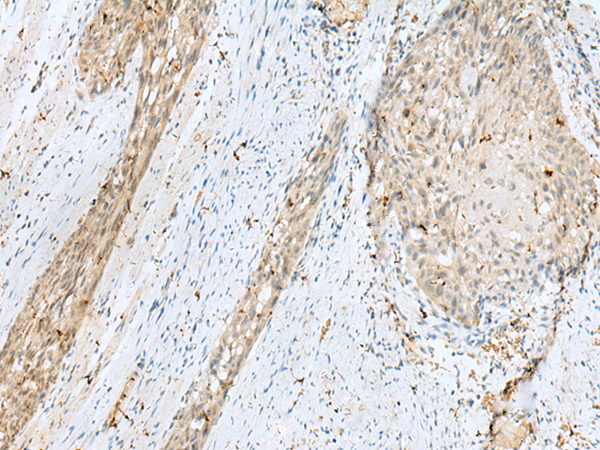

分类: 科研抗体货号: P09960别名: PC5; PC6; PC6A; SPC6应用: IHC反应种属: Human, Mouse, Rat